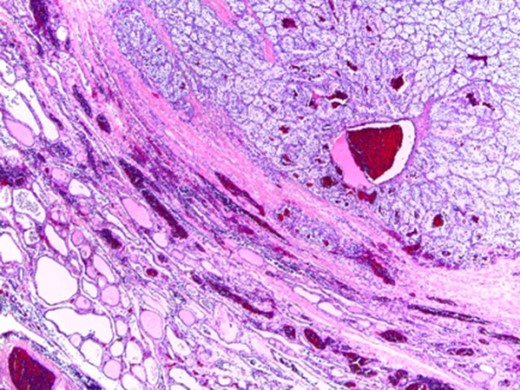

The histologic diagnosis was aided by the use of immunohistochemistry which was positive for PAX8 (Fig. 4) and CD10, and negative for thyroid transcription factor 1 (TTF-1) (Fig. 5), vimentin and chromogranin.

Importantly, the differential diagnostic consideration of a metastatic clear cell carcinoma within the clear cell parathyroid gland parenchyma may prove challenging since both tumors could be PAX8 and RCC immunoreactive [8,9]. However, a positive reaction with CAIX and CD10 and a negative reaction with chromogranin and parathyroid hormone studies can help confirm a RCC origin [4,9].